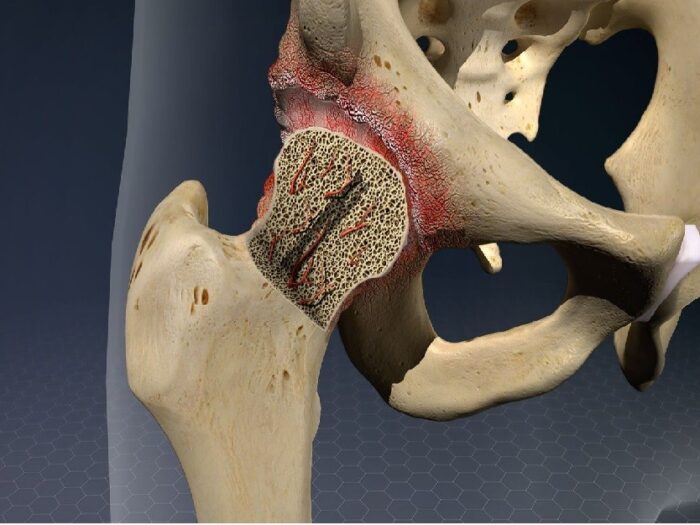

Avascular necrosis (AVN) is a medical condition that results in the death of bone tissue due to a lack of blood supply. It can cause severe pain and disability, and may even lead to long-term complications if not treated promptly and properly. This condition most commonly affects the bones in the hips, but it can also affect other joints such as those in the shoulders, knees, and ankles. While there are certain risk factors for developing AVN such as alcohol use disorder or steroid use, this disease can also occur spontaneously without any known cause. With early diagnosis and treatment, however, there is potential for slowing or halting AVN progression.

Avascular necrosis (AVN) is a condition where the bones start to die due to a lack of blood supply. It is a serious and potentially disabling condition that affects the joints, particularly those in the hips, shoulders, and knees. The exact cause of avascular necrosis can vary but there are three primary factors associated with this disorder: trauma, medical conditions and medications.

Avascular necrosis (AVN), also known as osteonecrosis, is a medical condition in which poor blood supply to the bone leads to bone death. It can cause severe pain and joint instability, and if left untreated can lead to disability due to joint destruction. The exact cause of AVN is unknown but it may be linked to certain medical conditions or medications that reduce blood flow.

Avascular necrosis, also known as osteonecrosis or ischemic bone necrosis, is a serious medical condition where there is a loss of blood supply to an area of the bone. This leads to cell death and eventual destruction of the affected bones. Diagnosis of avascular necrosis can be difficult because it does not always show up on traditional X-rays, and symptoms may not appear until extensive damage has already occurred. In this article, we will discuss the various methods used for diagnosing avascular necrosis.

Avascular necrosis (AVN), also known as osteonecrosis, is a condition that results in bone death due to a lack of blood supply to the bones. It can occur in any joint but most commonly affects the hip, knee, shoulder, and ankle joints. Treatment for AVN depends on the severity of the condition and may include medications, physical therapy exercises, or surgery.